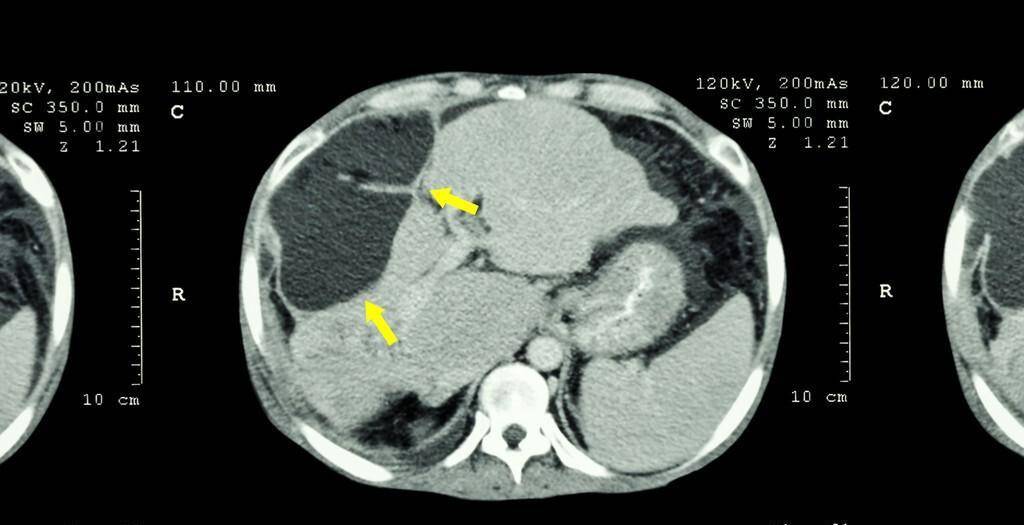

後來她對腫瘤進行了CT掃描,卻發現老人的腫瘤縮小了1.8倍,醫生聽到後,便詢問她的飲食習慣。

一、肝病有沒有可能自性消失,目前有沒有確切的證據資料?

根據歐洲的系統性文獻,不做任何的治療,確實是有機會縮小肝病,機會非常低。

肝病在人體內,也需要血液供應營養,如果用藥物送到腸胃阻止肝病細胞獲得血液,肝病細胞就會傷亡。